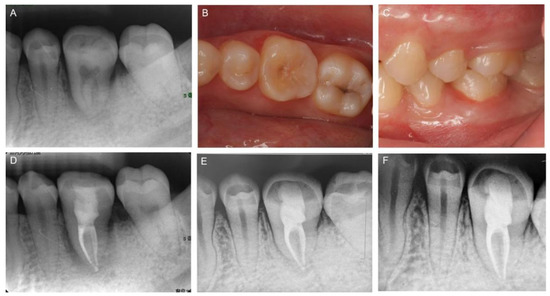

2. Case Report

2.1. Clinical Examination and Treatment Planning